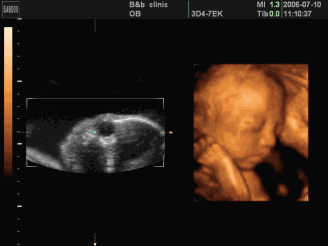

四维彩超是啥?

在专业领域上,四维多普勒超声是一种最大化直接了解到腹中婴儿身体状态的一种有效检查方式。

在对孕妇进行四维多普勒超声检查时,医护人员可以检查婴儿发育是否正常,包括器官是否发育正常,脸部特征和头部是否是正常。

另外,用于孕期内检查测试的四维多普勒超声仪器是按照人体工程学设计的,无需担心像微波镭射,电磁辐射会影响健康的辐射等诸多问题。孕妇可以安心使用四维多普勒超声了解腹中婴儿的发育状况。